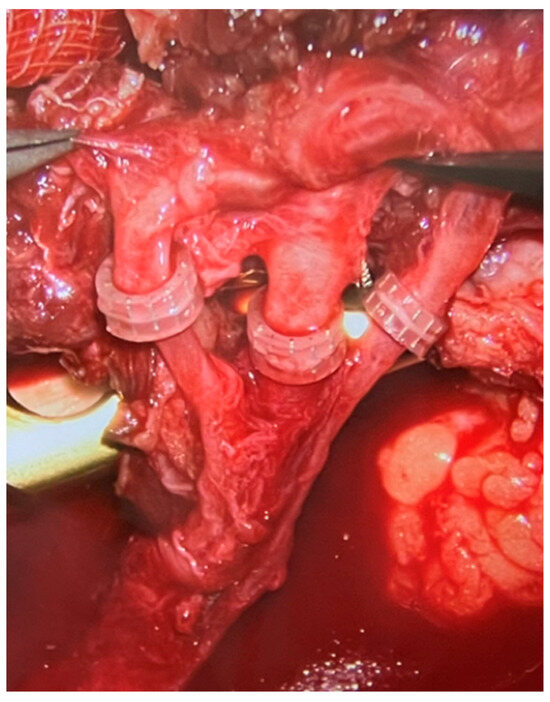

In every case, a combination of fibula free flap (FFF) with bone allograft, also known as the Capanna technique, was applied. Intraoperative photographs of the fibula free flap harvest are presented in Figure 1. All flaps were harvested as osteocutaneous flaps, including a skin paddle to facilitate postoperative clinical monitoring of fibula graft viability and to eliminate the need for imaging studies to assess the blood supply to the fully buried bony part of the flap.

The microvascular anastomoses were performed according to the available local vessels. Most commonly, the anastomoses were performed in end-to-end fashion to anterior tibial vessels. What needs to be emphasized is that in every case we performed two venous anastomoses—one to the deep venous system and one to the superficial venous system (most commonly the saphenous vein). Almost all arterial anastomoses were hand sewn using 9–0 or 10–0 nylon sutures. On the other hand, all veins were anastomosed using the microvascular anastomotic coupler system, as presented in the Figure 6 (Synovis Micro Companies Alliance, Birmingham, AL, USA). The average size of coupler used was 2.5 mm (range 1.5–4 millimeters).

4.3. Double Microvascular Venous Anastomoses

In microsurgery, the most common perioperative complication requiring urgent surgical intervention and frequently leading to partial tissue necrosis of the free flap is venous insufficiency, most commonly resulting from obstruction of the venous anastomosis [18]. Venous insufficiency is a much more common complication compared to arterial insufficiency regarding the free flaps. For this reason, in patients treated at the Institute of Mother and Child, in order to minimize the risk of the most common cause of flap perfusion impairment, two microsurgical venous anastomoses were performed during each procedure (Figure 6). One of them was performed in the deep venous system, the other in the superficial venous system.

Figure 6. Intraoperative photograph from a surgical microscope. Three microvascular anastomoses are visible—one arterial (in the middle) and two venous (on the sides), all performed with the use of a coupler device.